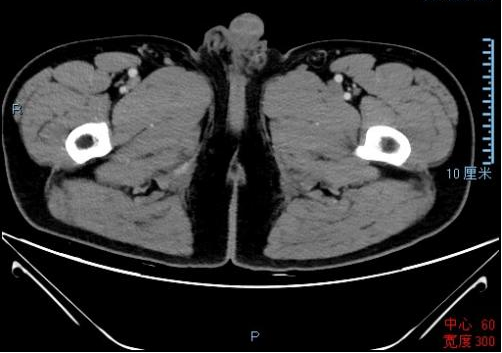

患者2月前偶有上腹隐痛,于当地医院行胃镜检查并活检(2021年7月31日),结果提示胃窦前壁、小弯交界处见一凹陷性深大溃疡,边界不平,上覆白苔。病理会诊(2021年8月9日)诊断为:中-低分化腺癌。

925.00.png

胃镜结果